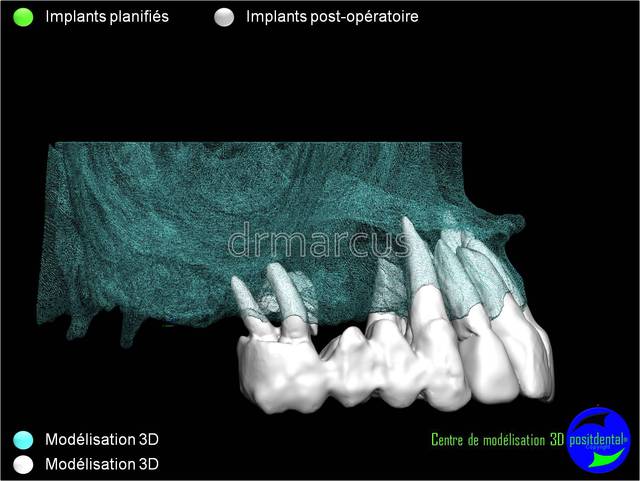

Analyse post-opératoire d’une MCI post-extractionnelle en chirurgie guidée

Cas clinique de drmarcus

Chirurgie : drmarcus

Imagerie 3D: POSITDENTAL

Guide chirurgical : POSITGUIDE

Dispositif de forage : POSITDENTAL

Implant : LEONE

Dommage que ce soit scanner avant et Cone-Beam après. Il est vrai que l’interprétation peut différer. Toutefois on voit la parfaite superposition des implants entre la planification et la réalisation. J'en conclue que le système Positdental est relativement fiable ;-))))